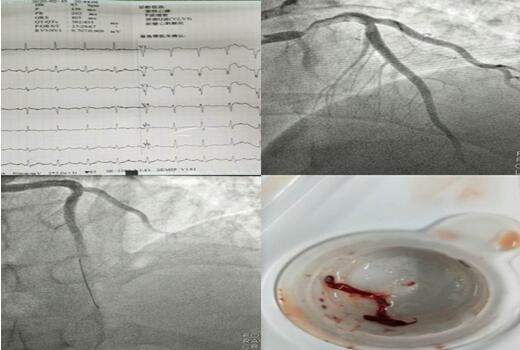

战疫当前,救死扶伤是每一位医务工作者的使命。心血管内科九病区于近日先后开展了三例急性心梗患者介入手术及一位扩张型心肌病患者行CRTD手术,挽救了患者生命,提高了患者的生活质量。疫情当前,全体医护人员坚守工作岗位,在防范新冠肺炎侵入的同时,暖心守护着每一位患者。

3个夜晚,3段急促的电话铃声打破了夜的寂静,电话另一端传来家属的焦急与担心。在接到胸痛中心电话的第一时间,3个夜晚的值班医生立即进行各项准备,通知当班护士备好让抢救物品及药品。患者被送达到科室同时启动导管室,进行术前相关检查,明确手术指征、与患者家属谈话说明病情。 3个不同的夜晚,无影灯下却站着同样的2个人,崔旭辉主任与张洪亮医生正在争分夺秒的抢救患者的生命。他们为其中两名患者进行了支架植入术,为另一名患者抽吸出血栓。术后3名患者生命体征均平稳,症状较前缓解。

2月11日,患者毛某行CRT-D术,该患者是一位69岁的男性,因劳力性胸闷、气短入院,多次因心衰于当地医院住院治疗,因疫情影响,辗转来到我院,入院后行冠脉造影提示正常,结合心脏超声,诊断为扩张型心肌病,给予强心、利尿、扩冠后心衰纠正但不明显。崔旭辉主任指出:该患者左室射血分数降低(LVEF28%),NYHA心功能Ⅳ级,左束支传导阻滞,QRS增宽大于120ms,有行CRT-D指征,即通过双心室起搏器同步刺激左、右心室再同步化治疗及埋置性心脏除颤器以改善心功能、治疗恶性心律失常。术后患者QRS波群时限缩短、症状明显改善。患者出院当天,科室收到来自患者家属的感谢信,这份感谢信是对我们最好的礼物,是对我们工作的肯定和赞许。